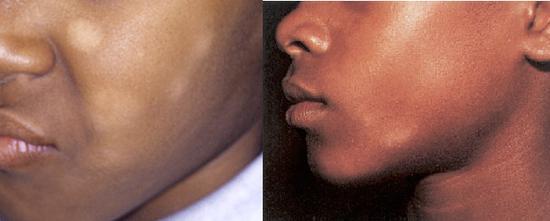

白色糠疹,这种疾病经常被误称为“虫斑”,其实这是错误的,这种白色皮疹和寄生虫一点关系都没有。皮疹在皮肤颜色深的人群中更加明显,表现如下图所示,边缘不规整的斑片状色素减退,常见于面部、颈部、躯干上部,直径在0.5-5cm,多无痒感。有时日晒后,会更加明显。

目前白色糠疹的原因不明,有些认为是湿疹后的一种表现,但是没有湿疹的孩子也会发生这种疾病。鉴于使用激素、保湿有效果,可以把白色糠疹认为也是一种皮肤炎症。另外,阳光暴晒,维生素缺乏可能会促进该症状。这种白色糠疹不严重,对身体没啥影响,无需治疗,自己也能好,白色糠疹可能持续数周到数月不等。